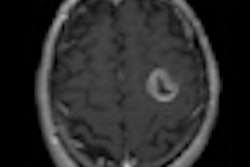

HIFU treatment uses ultrasound beams with short wavelengths and megahertz (MHz) frequencies focused into small-volume target areas to cause immediate coagulative necrosis of the targeted tissue. In theory, damaged tissue is supposed to be confined within the area of intended ablation, with no harm to overlying and adjacent structures.

All patients underwent general anesthesia for the procedure. Each target mass was ablated in multiple 5-mm sections with a 5-mm ablation margin. The HIFU treatment parameters included a therapy frequency of 0.8 MHz, a therapy power of 120-350 watts, a focus distance of 135 mm, and a mean focal field length of 9.8 mm and diameter of 1.1 mm.